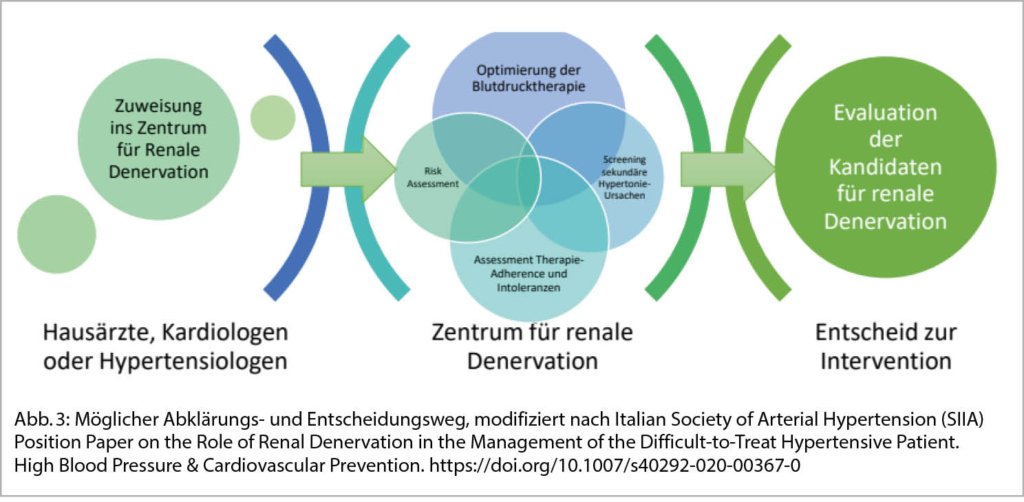

Einer epidemiologischen Erhebung zufolge, neigte etwa ein Drittel der Hypertoniepatienten dazu, eine RDN der Pharmakotherapie zur Behandlung des Bluthochdruckes vorzuziehen, wobei erwähnt bleiben muss, dass auch nach der RDN der grösste Anteil der Patienten weiterhin Medikamente einnehmen muss, da der Effekt in etwa einer pharmakologischen Monotherapie entspricht. Insbesondere jüngere Patienten, männliche Patienten, Patienten mit Nebenwirkungen und Patienten, die zugaben, sich nicht an die Therapie zu halten, neigten eher dazu, die RDN einer Pharmakotherapie vorzuziehen. Die Präferenz der Patienten für eine RDN-Behandlung war unabhängig von der Höhe des Blutdrucks und der Anzahl der blutdrucksenkenden Medikamente, wohingegen die Präferenz der Ärzte für eine RDN auf dem Stadium des Bluthochdrucks und der Anzahl der Medikamente beruht. Zusammenfassend empfehlen wir einen strukturierten Weg für den klinischen Einsatz der RDN. Da die Sichtweise der Ärzte und die Präferenzen der Patienten voneinander abweichen können, schlagen wir vor, einen standardisierten gemeinsamen Entscheidungsfindungsprozess einzuführen, um die beste Behandlungsoption für die Blutdruckkontrolle einschliesslich der RDN zu finden.

Insgesamt sollte die Vorabklärung, Indikationsstellung und Behandlung in Zentren erfolgen, welche ausreichend Erfahrung mit der Behandlung von therapierefraktären und sekundären Hypertonieformen und dann auch der Intervention haben sowie die nötige Überwachung und allfällige Behandlungen von Komplikationen innert nützlicher Zeit anbieten können (Abb. 3). So wird in Deutschland zum Beispiel über eine Akkreditierung von renalen Denervationszentren nachgedacht, um eine standardisierte und hohe Behandlungsqualität zu gewährleisten. Zudem sollten die behandelnden Patienten wissenschaftlich nachverfolgt werden.